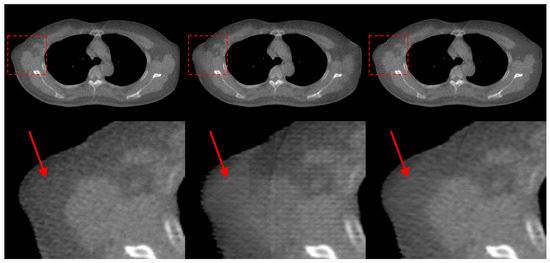

5. Discussion and Conclusions